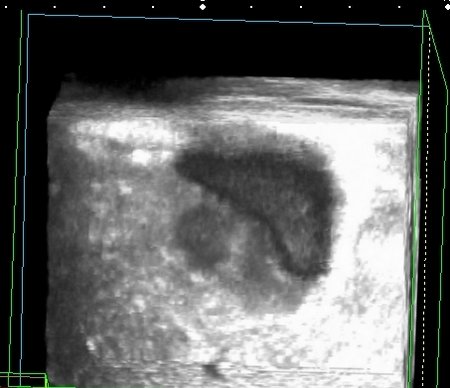

На УЗИ рядом с желчным пузырём определяется овоидное образование солидной струкутры с чёткими контурами.

При ЦДК кровоток в образовании не регистрировался, свободной жидкости в брюшной полости не было.

Предположил наличие удвоения желчного пузыря, с этим заключением пациент исчез из поля зрения.

Похож ли данный случай на удвоение? Должна ли содержаться желчь в добавочном пузыре? Буду благодарен за отклики.

Полазил в сети на предмет удвоения желчного пузыря. Ультразвуковая картина значительно зависит от уровня, степени удвоения и оттока желчи из удвоенной части желчевыводящей системы. Вероятно в моём случае могло быть фундальное удвоение или V - образный желчный пузырь с нарушением оттока из латеральной половины с общим пузырным протоком. Сосудистый рисунок в печени и её воротах изменён не был. В любом случае хирурги лечить его не собирались - клиники не было. Хотя описаны случаи камнеобразования и опухолей ( почему - то невином) в удвоенном ЖП.Инга писал(а):А что с протоками? Я так предполагаю, что должно быть тоже некое удвоение (р.s я не утверждаю, я предполагаю, я с удвоением ЖП не сталкивалась)